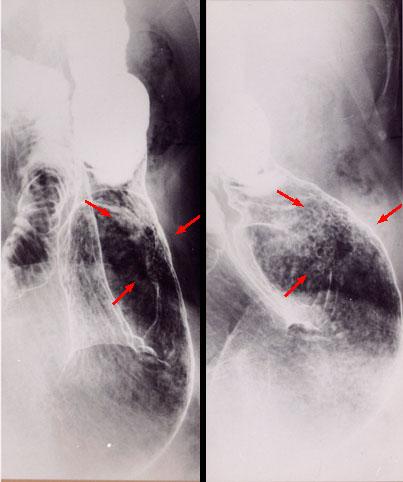

易与肿瘤混淆的炎症性及非肿瘤性疾患、病变

消化道淀粉样变性 (胃)

形态类似于表面凹陷型(IIc型)早期胃癌的消化道淀粉样变性

炎症性・溃疡性疾患/消化管淀粉样变性

胃(部位)/前庭

X线